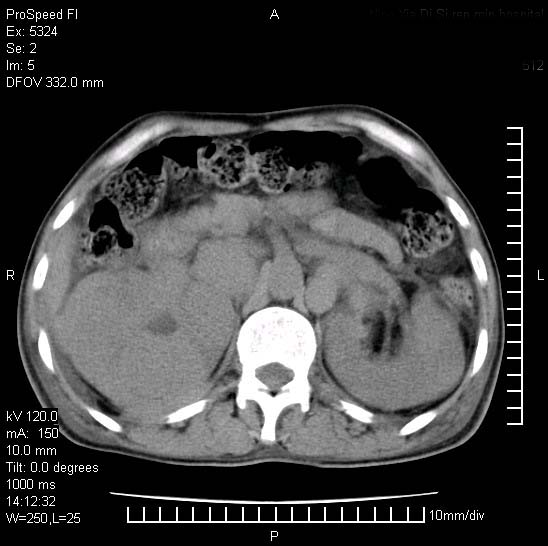

患者阴囊肿大14月,腰痛2个月,咳嗽,咳痰1周,患者现在肾功异常,做增强有些担心,我们用的是欧乃派克.

右侧肾癌伴腹膜后淋巴结转移!

右侧肾癌后腹膜转移,腹腔少量积液

腹膜后淋巴结肿大包饶腔静脉,双肾病变,建议增强

双肾均有软组织密度舯物,腹膜后淋巴结肿大包饶腔静脉------考虑为恶性占位病变,转移瘤可能。

左肾也有问题呀///

支持:双肾均见软组织密度肿块影,腹膜后淋巴结肿大包绕腔静脉------考虑为恶性占位病变,转移瘤可能。

1)考虑双肾恶性肿瘤(肾癌?)。2)腹膜后淋巴结肿大,多为肿瘤转移所致。

腹腔积液,双肾均有稍高密度肿块,主动脉旁广泛淋巴结肿大,融合,无显著肿块坏死征像,多考虑淋巴瘤累及双肾,不排除肾癌伴转移(肾癌这么大应该较多坏死了),另阴囊肿大,不知是实质肿大还是阴囊积液,如是是积液,多为腹腔肿块压近睾丸静脉所致,如是是实性的,多为淋巴瘤

1、淋巴瘤,双肾转移瘤;2、双侧肾癌,伴有腹膜后淋巴结转移。

双肾周围及腹膜后改变符合恶性病变,现在关键是要明确阴囊肿大的原因,是否为肿瘤性病变.如阴囊为恶性肿瘤那一切用转移即可解释,如阴囊为水肿改变,那需重新分析检查明确.

双肾均有软组织肿块伴腹膜后淋巴结肿大融合,右侧结肠旁沟积液;考虑恶性肿瘤。转移瘤?淋巴瘤?

阴囊肿大是实质性的么,为什么不扫阴囊,此扫描做的是什么部位,肾脏没包括全,也可以考虑生殖系统肿瘤转移

双肾增大,腹膜后多发肿大淋巴结影.首先考虑淋巴瘤.

双肾增大,结合腹膜后淋巴结肿大,考虑双肾恶性肿瘤并转移可能。

双肾癌并腹膜后淋巴结转移

考虑恶性淋巴瘤侵及双肾,腹膜后淋巴结肿大。